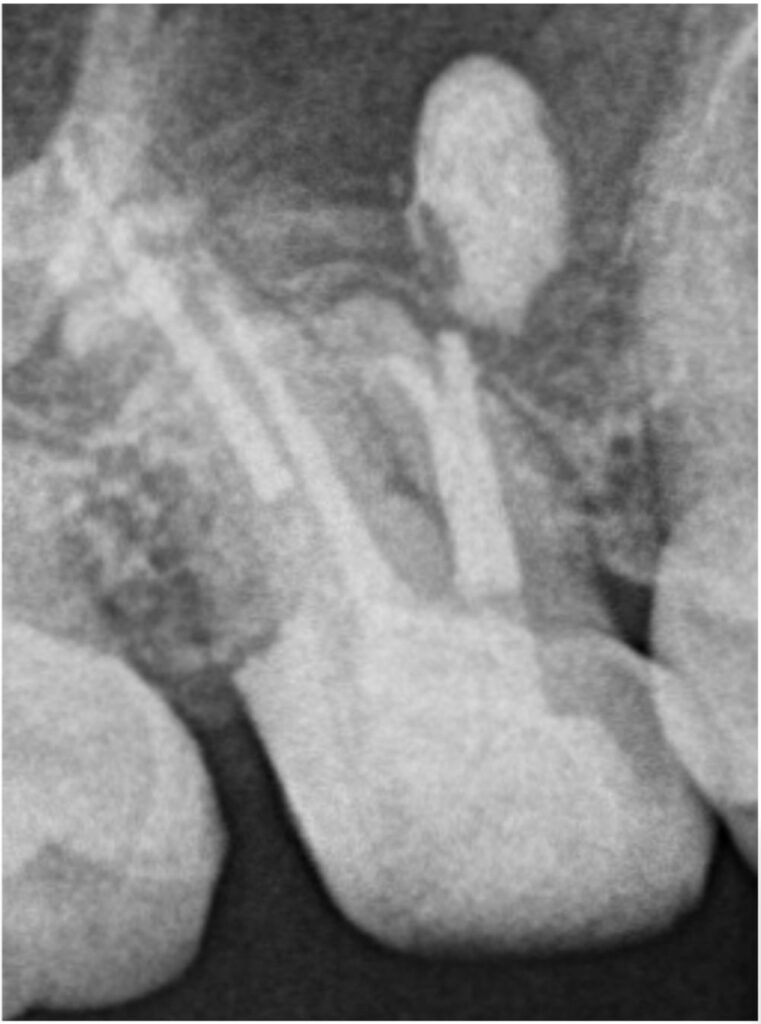

右上6番は、近心根管のパーフォレーション(穿孔)が疑われ、そこから根尖孔外へレントゲン的に白く写る不透過性物質の押し出しが確認できました。性状から、貼薬材料あるいは根管充填に使用するシーラーであると推測されました。

根管内の古い詰め物をすべて除去し、本来の異なる方向に穴があいているパーフォレーション部位に対しては、MTAセメントを使用して穿孔封鎖を行いました。

治療は2回で完了し、飛び出ている材料の状態も含め、経過観察となりました。

治療前にはっきりと写っていた根の先の材料ですが、術後12ヶ月では完全に消失しています。治療前には強く感じていた鈍い痛みもなくなり、良好な状態を維持しています。